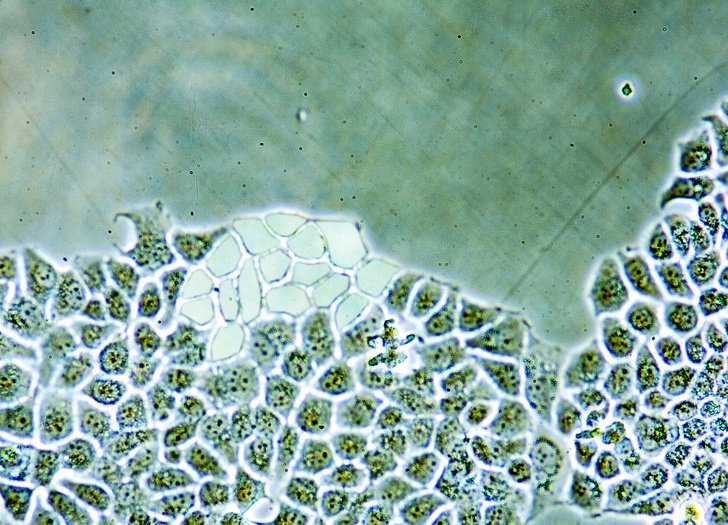

Хворі на астму можуть сподіватися на життя без інгаляторів

Зліва – здорові бронхи, праворуч – при астмі.

Випробування препарату під назвою Февіпіпрант , що з’явився кілька років тому, наближаються до фінальної стадії. Це єдиний сьогодні лікарський засіб, який здатний замінити і інгалятори. Февіпіпрант здатний боротися зі звуженням дихальних шляхів, викликаним збільшенням гладких тканин бронхів, що провокує напади астми і, як наслідок, може призвести до смерті.